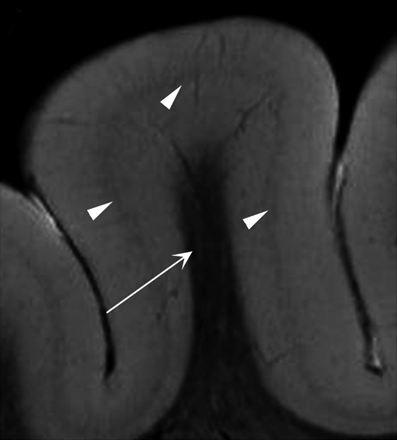

结合7 t磁共振成像和病理研究正常和发育异常的患者样本框架

作者研究了13个标本使用t2加权成像和王仁贵期间和之后进行固定,使用7 t实验扫描仪。高分辨率体外MRI使皮层组织在正常和病理的研究领域和可能与患者的诊断框架。

看到p。1177年